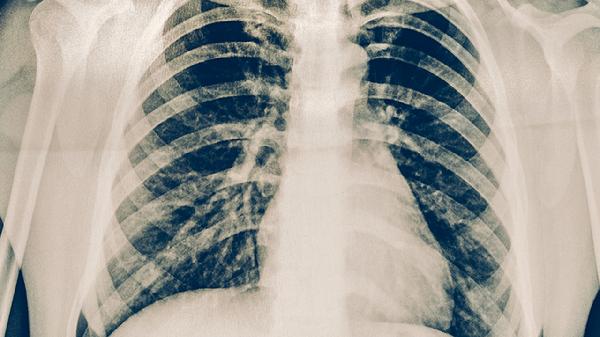

肺结核的复查频率主要依据治疗阶段和个体差异而定。初始强化治疗阶段需每1-2个月复查痰涂片、胸部影像学及肝肾功能,评估药物疗效与副作用。病情稳定后进入巩固治疗期,复查间隔可延长至2-3个月。若出现药物不良反应如肝功能异常,需缩短复查周期至2-4周。儿童、老年人或合并其他疾病的患者,可能需更频繁监测。复查项目通常包括痰结核菌检查、胸部X线或CT、血常规、肝肾功能等,必要时增加听力或视力检查。治疗期间症状加重或新发不适需立即就医。